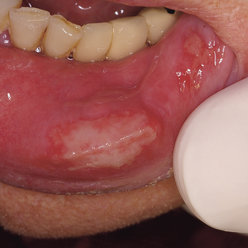

Traumatic ulcer

This is a type of ulcer which is caused by traumas to the oral cavity by various means including:

Differential diagnosis

oral squamous cell carcinoma

TB ulcer

Major recurrent aphthous ulcers